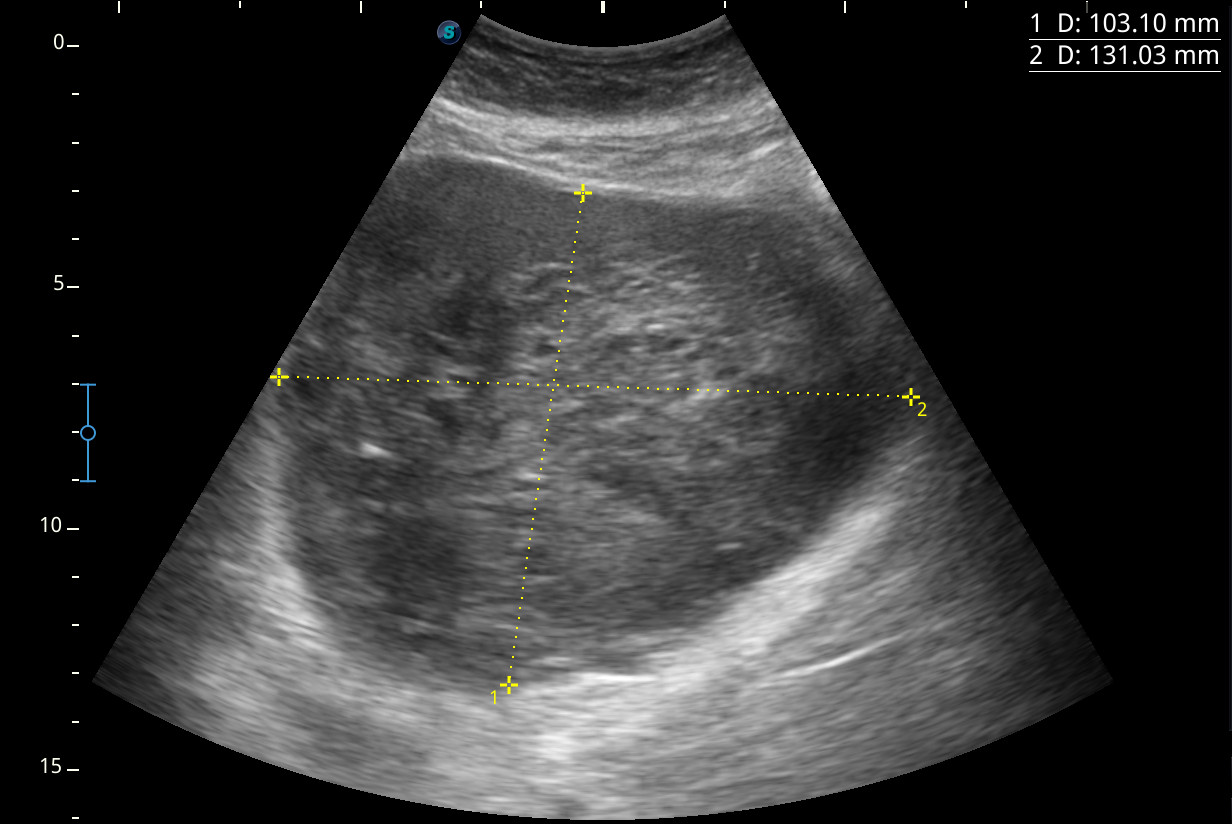

Se visualiza una masa heterogénea de unos 10 x 13 cm aproximadamente de diámetro con posibles focos necróticos y captación Doppler color, de dudosa organodependencia, que podría corresponder a un sarcoma retroperitoneal.